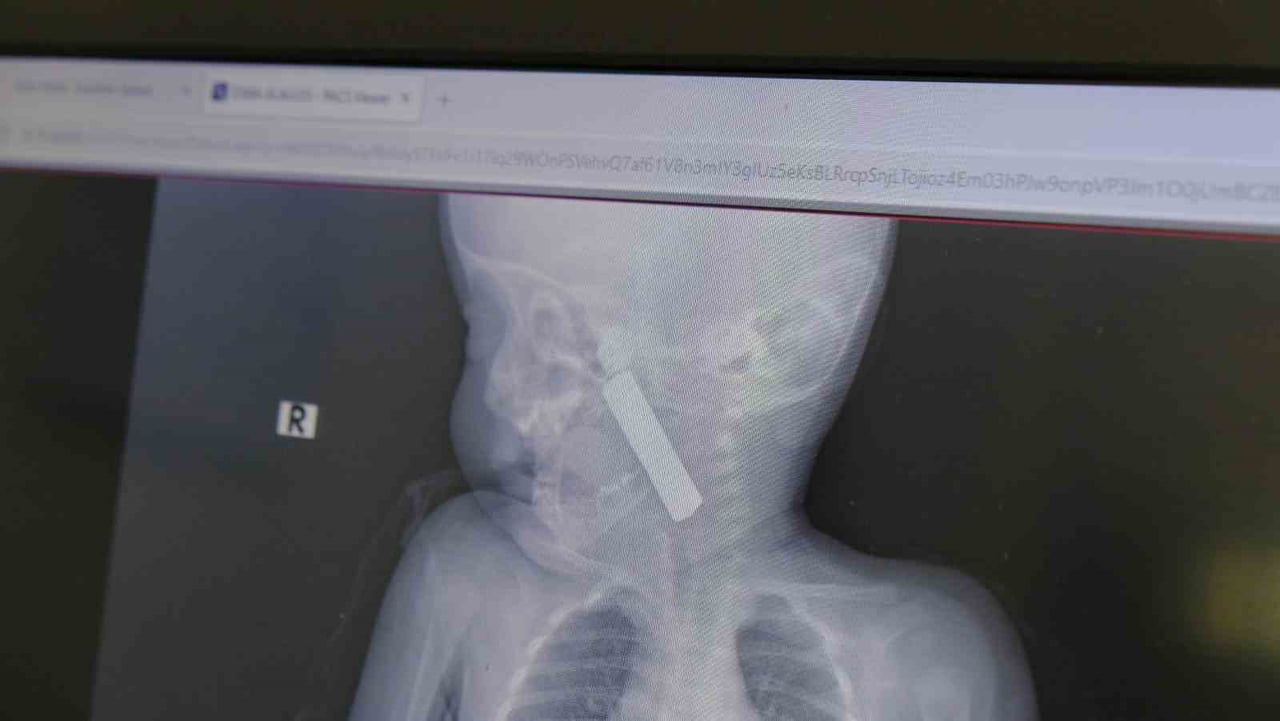

Karaman Eğitim ve Araştırma Hastanesi acil servisine kusma şikayetiyle getirilen 6 aylık E.A.'nın boğazında yapılan muayene ve tetkiklerde kumanda pili tespit edildi. Solunum sıkıntısı yaşayan bebek, Çocuk Cerrahisi Uzmanı Doç. Dr. Mehmet Uysal tarafından gerçekleştirilen ameliyatla pil çıkarıldı.

"Acil polikliniğimize kusma şikayeti ile 6 aylık bir kız bebek getirilmiş ve bize haber verildi. Biz de vakit kaybetmeden geldik, hastamızı gördük. Yapılan tetkikler sonucunda, ağız tabanına oturan ve yemek borusunun birinci darlığına kadar uzanan, kumanda pili dediğimiz bir pille karşılaştık. Filmde ve muayenede bunu gördük. Hastayı ilk gördüğümüzde bayağı siyanotik durumda, solunum sıkıntılıydı ve oksijen satürasyonu 90 civarındaydı. Böyle olunca bir an önce beklemeden hızlı bir şekilde ameliyathaneye götürdük. Orada ameliyathanedeki anestezi uzmanlarımız ve personel bize yardımcı oldu, hasta hızlı bir şekilde entübe edildi. Ondan sonra da laringoskop ve magill forseps dediğimiz malzemelerimizle bu yabancı cismi çıkarmış olduk. Bir an evvel müdahale ettik, iyi ki müdahale ettik, orada ağız tabanında, özellikle ön kısmında hasar oluşmuştu. Müdahale sonrasında da hastanın solunum problemleri bir süre devam etti, bu yüzden 24 saat takip ettik. Herhangi bir problem oluşmayınca 24 saat sonra kontrole gelmek üzere hastayı taburcu ettik" diye konuştu.